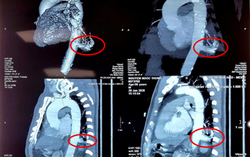

Bệnh viện Bình Dân (TPHCM) vừa thực hiện thành công trường hợp phẫu thuật robot cắt thùy dưới phổi trái điều trị bệnh lý phổi biệt lập nội thùy. Đây cũng là trường hợp phổi biệt lập được điều trị bằng phẫu thuật robot được báo cáo đầu tiên tại Việt Nam.